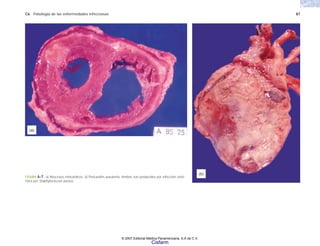

FIGURA 6-7. a) Abscesos miocárdicos. b) Pericarditis purulenta. Ambos son producidos por infección sisté-

mica por Staphylococcus aureus.